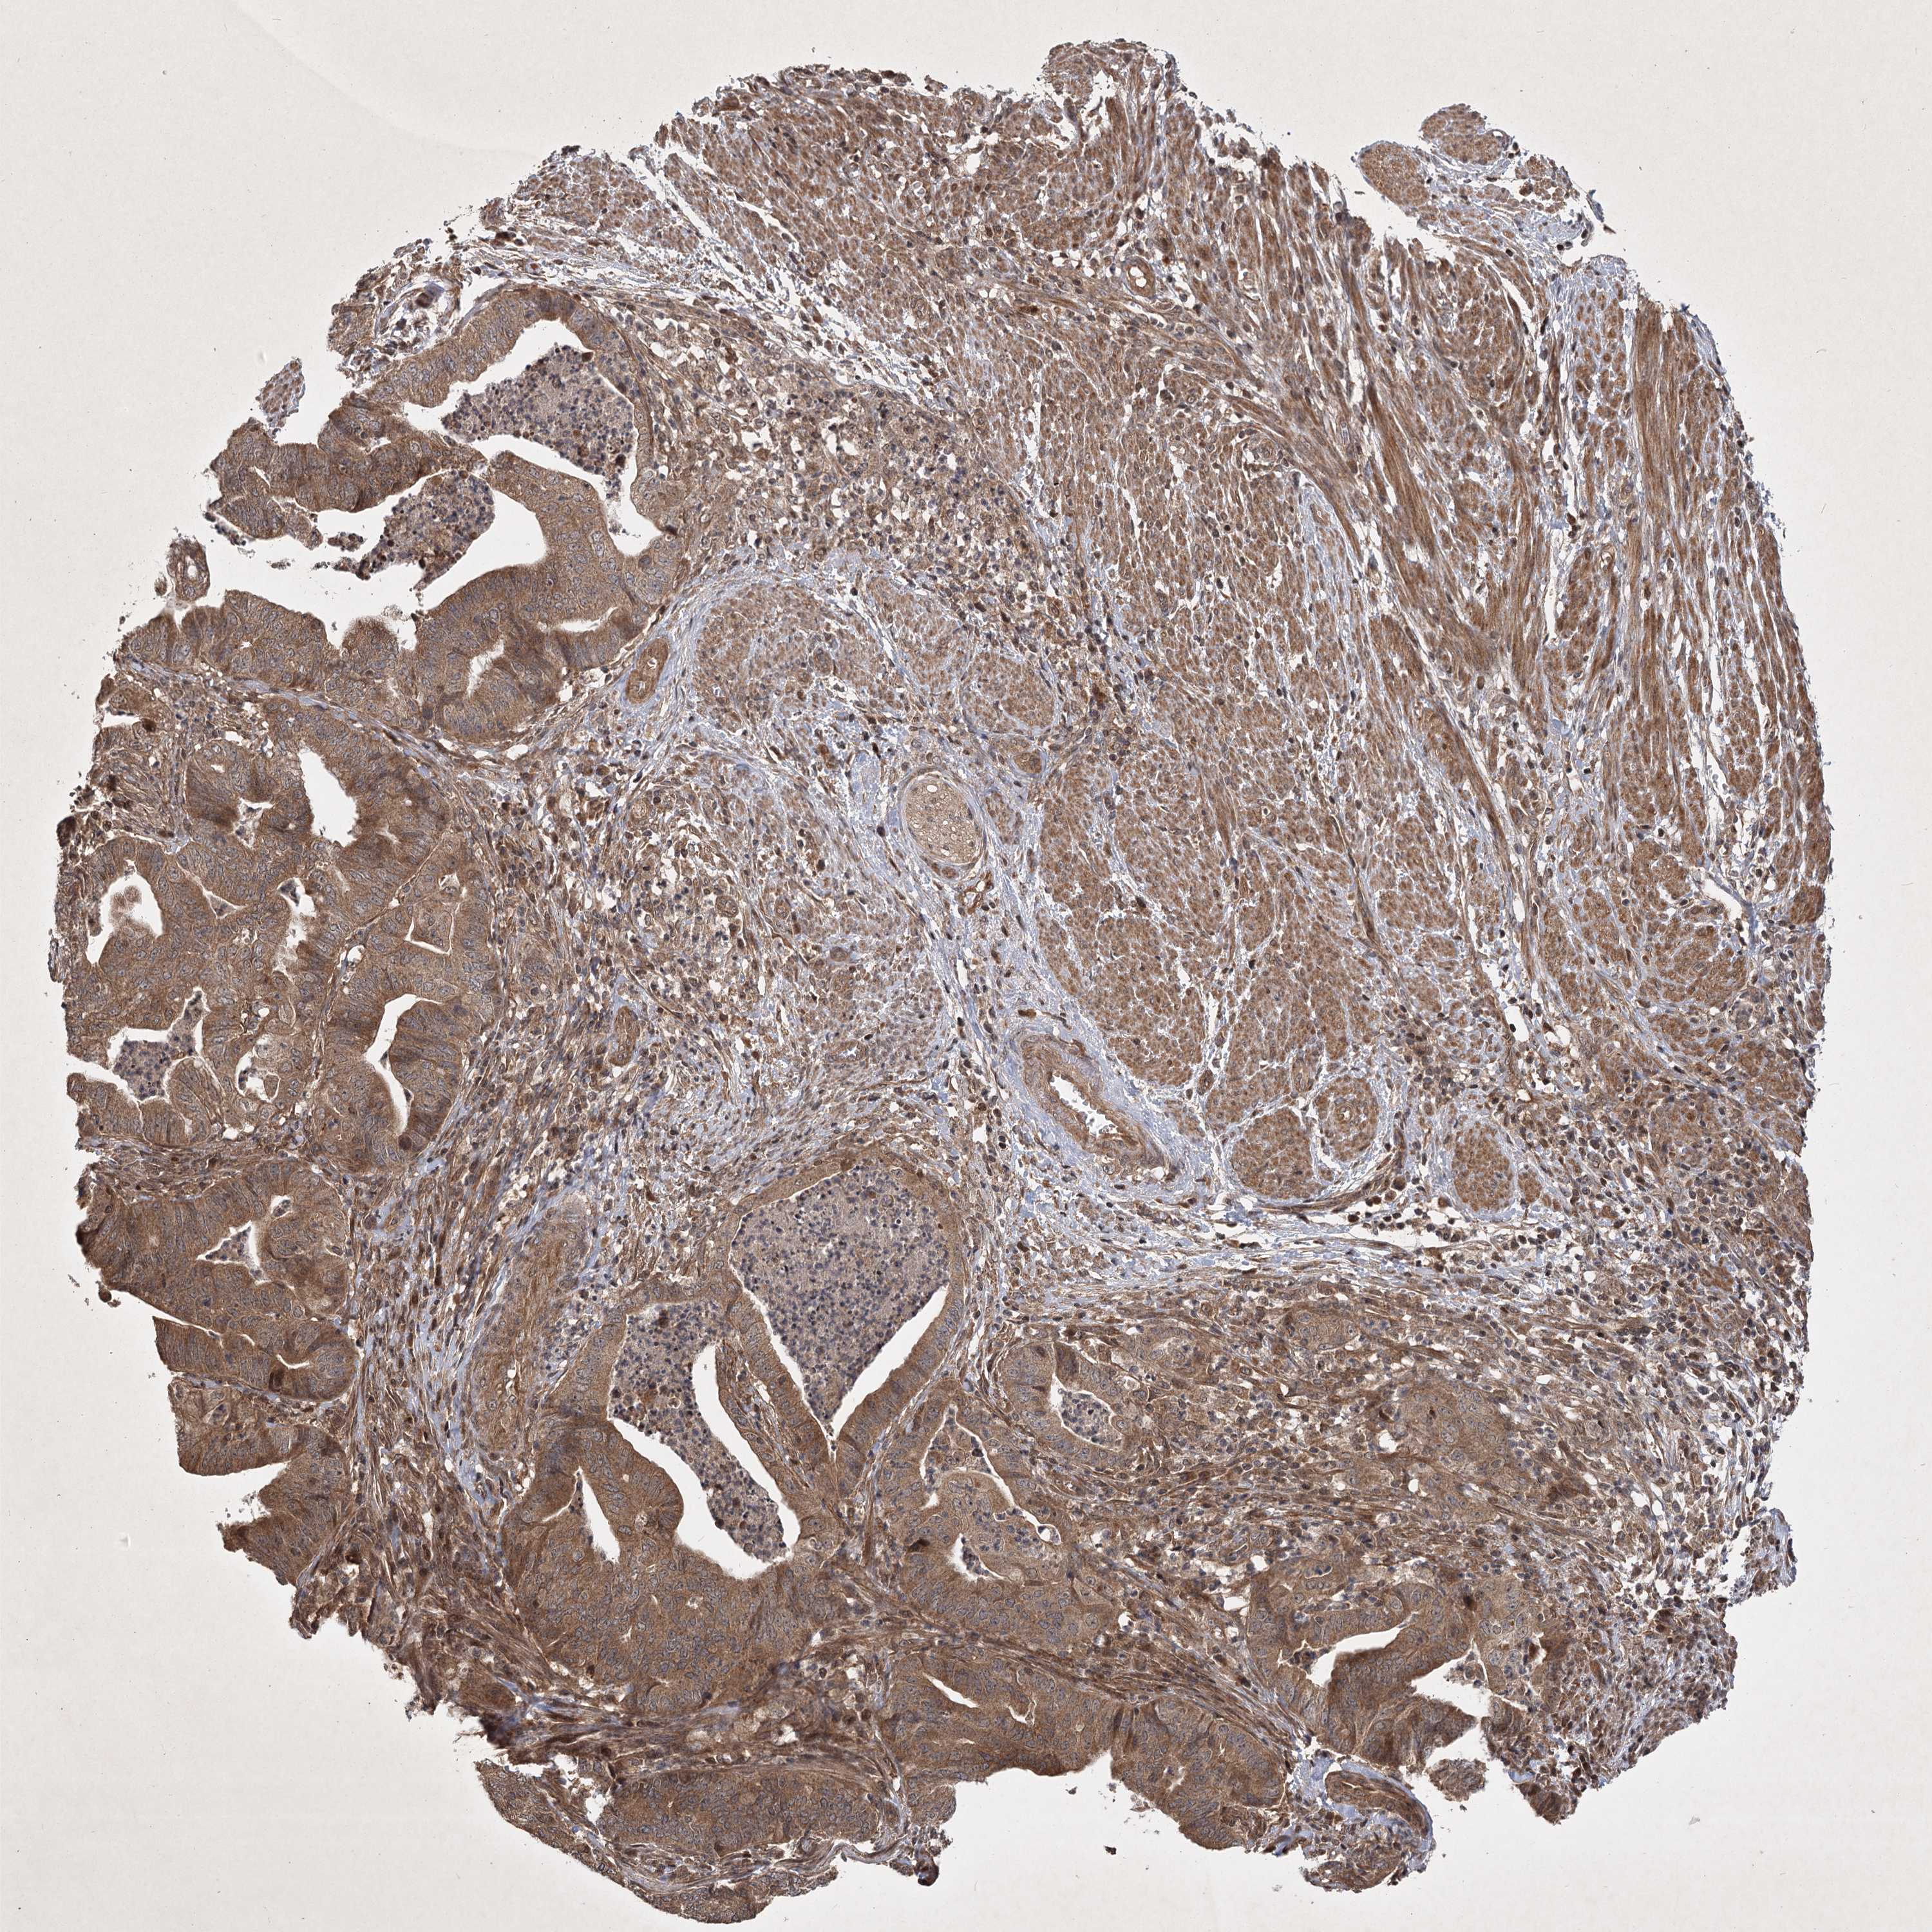

ENDOMETRIAL CANCER - Protein expressioni

A mouse-over function shows sample information and annotation data. Click on an image to view it in a full screen mode. Samples can be filtered based on level of antibody staining by selecting one or several of the following categories: high, medium, low and not detected. The assay and annotation is described here.

Note that samples used for immunohistochemistry by the Human Protein Atlas do not correspond to samples in the TCGA dataset.

Antibody stainingi

Antibody staining in the annotated cell types in the current human tissue is reported as not detected, low, medium, or high, based on conventional immunohistochemistry profiling in selected tissues. This score is based on the combination of the staining intensity and fraction of stained cells.

Each image is clickable and will lead to virtual microscopy that enables deeper exploration of all samples and also displays staining intensity scores, fraction scores and subcellular localization as well as patient and tissue information for each sample.

Antibody CAB033861

Staining

High

Medium

Low

Not detected

Intensity

Strong

Moderate

Weak

Negative

Quantity

>75%

75%-25%

<25%

None

Location

Nuclear

Cytoplasmic/membranous

Cytoplasmic/membranous,nuclear

Adenocarcinoma, NOS

Adenoma, NOS